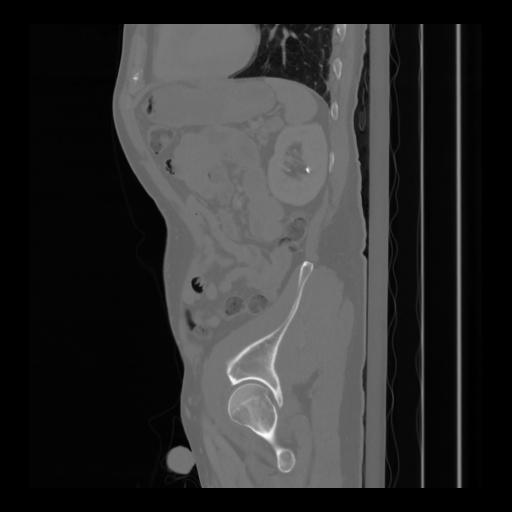

36 CUERPO,CE,Sagittal,3.000,CUERPO,Sagittal,